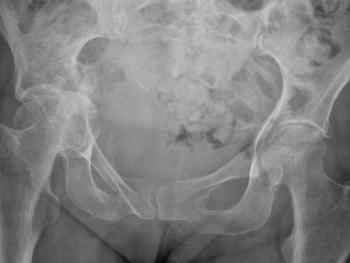

Clinical cases: variations of Exeter stem size and offset copes with almost all abnormal anatomies.

Figure 7 & Figure 8: DDH case with bowed femur and over-riding GT.